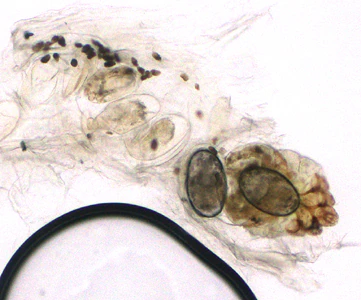

A patient presented to a local hospital with encrusted lesions on his arms and legs. A skin scraping was made and examined unstained at 40x magnification. Figures A and B show what was observed by the attending microbiologist. The images were sent to the DPDx Team for diagnostic assistance. What is your diagnosis? Based on what criteria?

Figure A